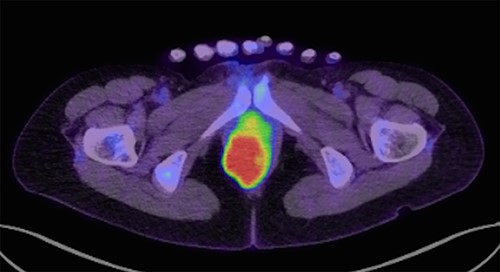

A 43-year-old female underwent pelvic magnetic resonance imaging (MRI) for uterine myoma that incidentally revealed a 4.6 × 2.8 cm soft tissue mass in the right perineal area (Fig. 1A). Rectal endoscopy showed a submucosal tumor just above the anal canal (Fig. 1B). FDG-PET/CT scan revealed an anorectal tumor with very high 18F-FDG uptake (SUVmax = 17.9; Fig. 2). As aspiration cytology and needle biopsy were inconclusive, we planned to perform trans-perianal tumor resection.

FDG-PET/CT (transverse section) show FDG accumulation in a mass with maximum standardized uptake of 17.9.